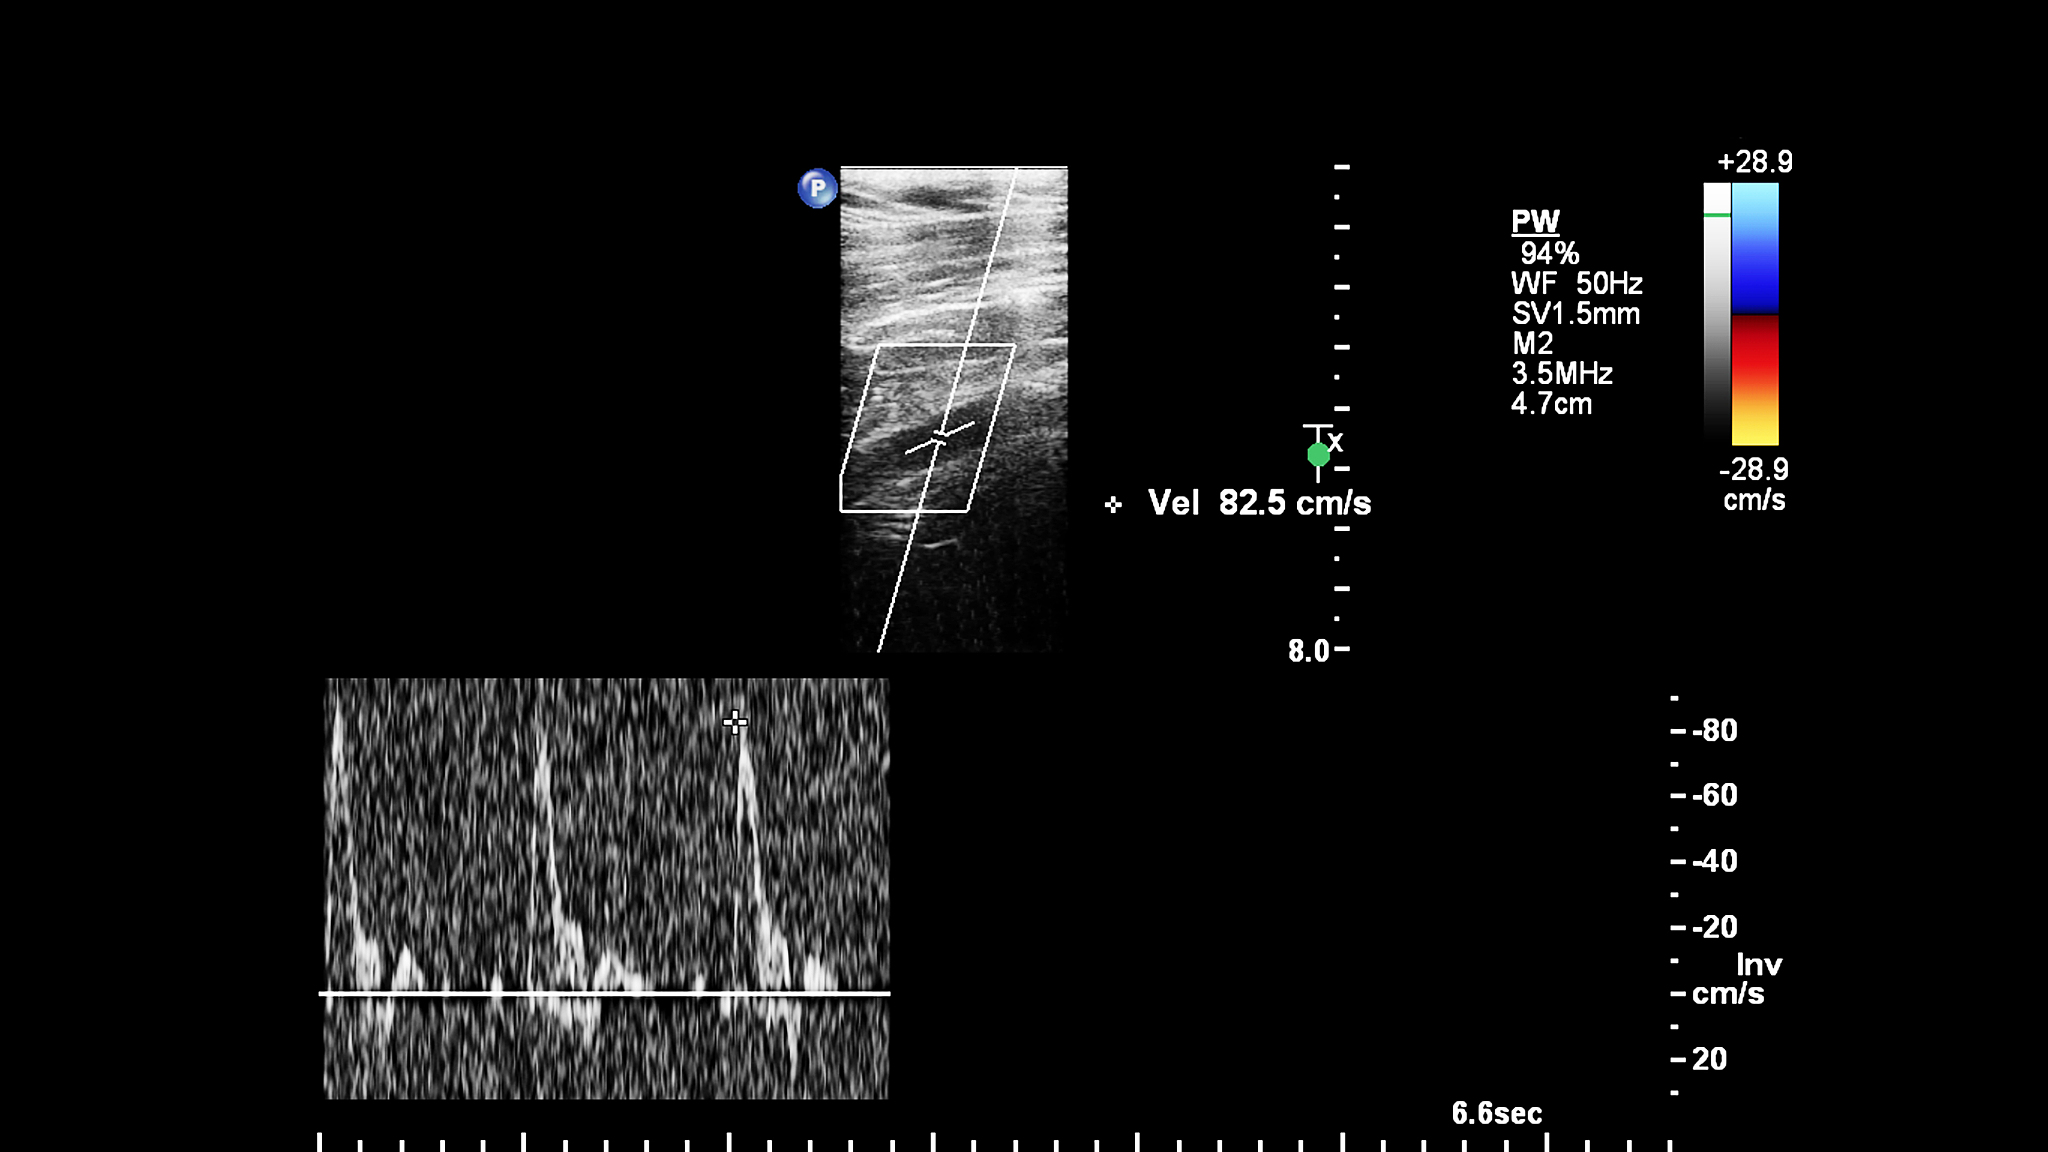

血管内超声诊断导管是一种用于检查血管内部情况的医疗设备,可以通过导管将超声换能器放置在需要检查的位置,以获取更准确的超声图像。而提高换能器的中心频率可以带来以下几个项目的必要性:

1. 提高图像分辨率:换能器的中心频率越高,其所能接收到的高频信号越多,可以提高图像的分辨率。高分辨率的图像可以更清晰地显示血管内部的细节结构,有助于医生更准确地诊断病变。

2. 改善深部组织成像:随着换能器中心频率的提高,其穿透能力会下降,但对于浅表的血管或病变来说,这并不是问题。相反,较高的中心频率可以更好地捕捉到浅表组织的细节,提高深部组织成像的质量。

3. 提高信噪比:换能器的中心频率越高,其接收到的信号越强,相对于噪声的信噪比也会提高。这样可以减少噪声对图像质量的影响,使医生能够更准确地分辨病变。

总之,提高血管内超声诊断导管换能器的中心频率可以提高图像的分辨率和质量,有助于医生更准确地诊断血管内部的病变。